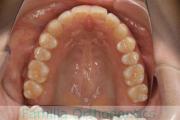

上の前歯の並びが気になるのできれいにしたい、ということで来院されました。マウスピース型矯正装置のひとつ、インビザライン/InvisalignR(薬機法および医薬品副作用被害救済制度の対象外)を用いて治療しました。

非抜歯で2年弱、20回程度の通院で治療が完了しました。

マウスピース矯正は、患者さんの協力に治療結果が左右されるところはリスクと言えるかもしれません。